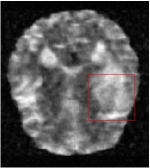

Qualitative comparison between conventional and Meta-learning methods are shown in Figure 1 and 3, which display the reconstructed MR images of the same slice for T1 and T2 respectively, we label the zoomed-in details of HGG in the red boxes. We observe the evidence that conventional learning is more blurry and lost sharp edges, especially in lower CS ratios. From the point-wise error map, we find meta-learning has the ability to reduce noises especially in some detailed and complicated regions comparing to conventional learning.

In this section, we test the generalizability of the proposed model that tests on unseen tasks. We fix the well-trained task-invariant parameter and only train for sampling ratios 15%, 25% and 35% with radio masks and sampling ratios 10%, 20%, 30% and 40% with Cartesian masks. In this experiment, we only used 100 training data for each CS ratio and apply a total of 50 epochs. The averaged evaluation values and standard deviations are listed in Table 5.4 and 5.4 for reconstructed T1 and T2 brain images respectively that proceed with radio masks, and Table 5.4 shows the qualitative performance for reconstructed T2 brain image that applied random Cartesian sampling masks. In T1 image reconstruction results, meta-learning improved 1.6921 dB in PSNR for 15% CS ratio, 1.6608 dB for 25% CS ratio, and 0.5764 dB for 35% comparing to the conventional method, which in the tendency that the level of reconstruction quality for lower CS ratios improved more than higher CS ratios. A similar trend happens in T2 reconstruction results with different sampling masks. The qualitative comparisons are illustrated in Figure 2, 4 and 5 for T1 and T2 images tested in skewed CS ratios in radio masks, and T2 images tested in Cartesian masks with regular CS ratios respectively. In the experiments that conducted with radio masks, meta-learning is superior to conventional learning especially at CS ratio 15%, one can observe that the detailed region in red boxes keeps edges and is more close to the true image, while conventional method reconstructions are hazier and lost details in some complicated tissue. The point-wise error map also indicates that Meta-learning has the ability to suppress noises.

Training with Cartesian masks is more difficult than radio masks, especially for conventional learning where the network is not very deep since the network only applied three convolutions each with four kernels. Table 5.4 indicates that the average performance of meta-learning improved about 1.87 dB comparing to conventional methods with T2 brain images. These results further demonstrate that meta-learning has the benefit of parameter efficiency, the performance is much better than conventional learning even if we apply a shallow network with small size of training data.